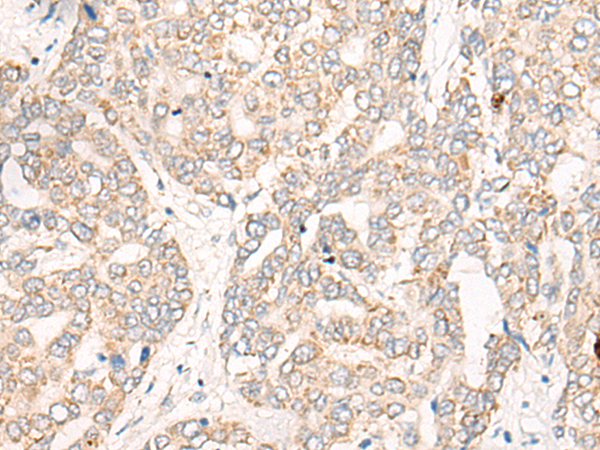

The image is immunohistochemistry of paraffin-embedded Human liver cancer tissue using 46990(CREB3L2 Antibody) at dilution 1/25. (Original magnification: ?00)

,